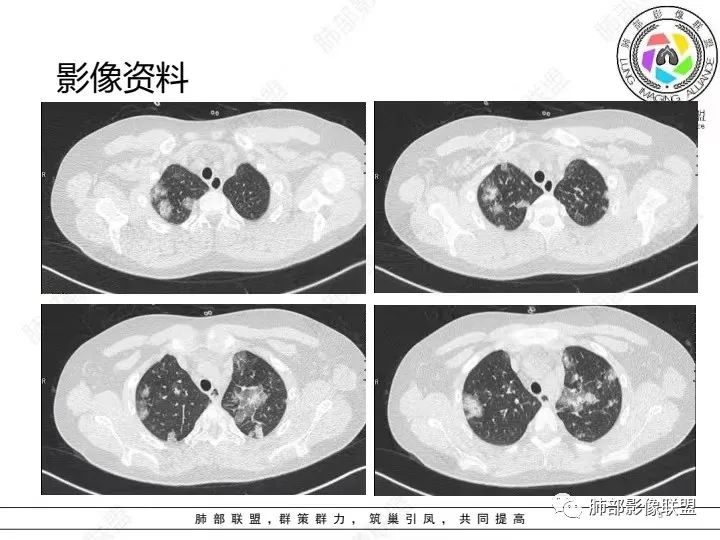

【病例】血源性金黄色葡萄球菌性肺炎1例CT影像

1.男性少年儿童,外伤后髋部疼痛,畏寒发热、咳嗽、呼吸困难。

休克血压。CRP、PCT明显升高。血气为代谢性酸中毒、呼吸性碱中毒。

2.影像上肺多发混合密度片影,随机分布,胸膜下分布优势,病灶边界大多隐约可辨,偏柔和,动脉血管影穿行,未见钙化、液化空洞、或明确气囊影,未见树芽征。

3.双侧胸腔未见积液。双肺门及纵隔未见增大淋巴结。

4.肝左右叶密度减低,未见结节影、块影或液化区。